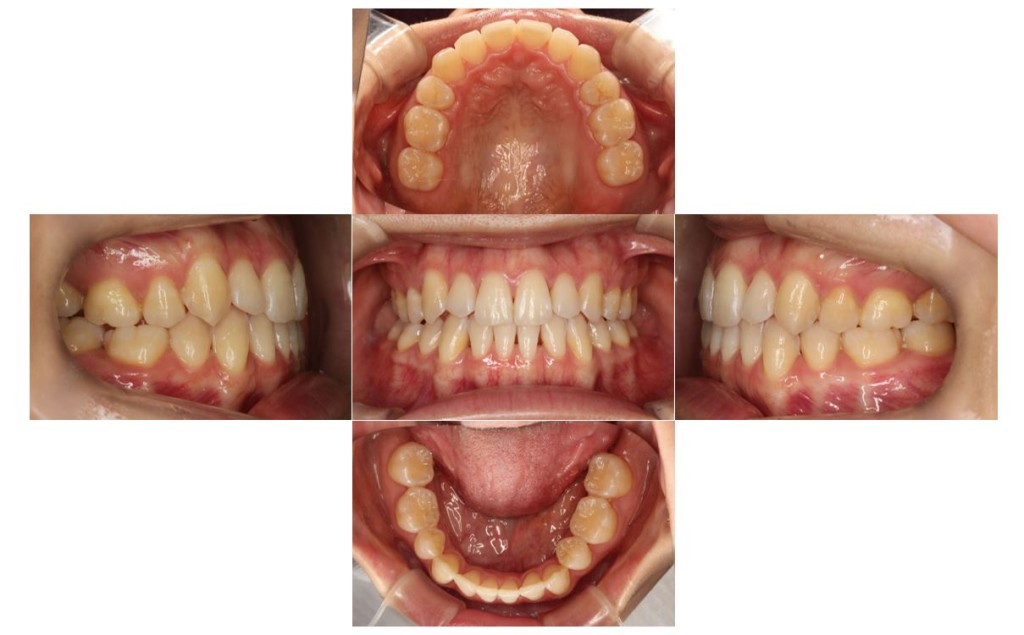

当院の症例

| 主訴 | 下の歯が、上の歯より前に出ていて顎が出ているのが気になる。受け口を治したい。でこぼこもあり歯磨きにしくいので、虫歯予防のためにも綺麗に並べたい。 |

| 治療期間 | 2年2ヶ月(29回) |

| 抜歯 | 有(左上4、左下5、上下親知らず4本) |

| 矯正の装置 | 裏側矯正(舌側矯正) |